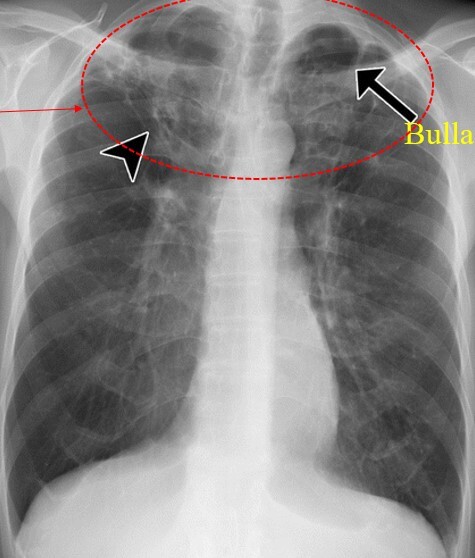

Q

Pt has Hx of TB and their CXR shows bullae. What’s happening

A

Reactivation of TB